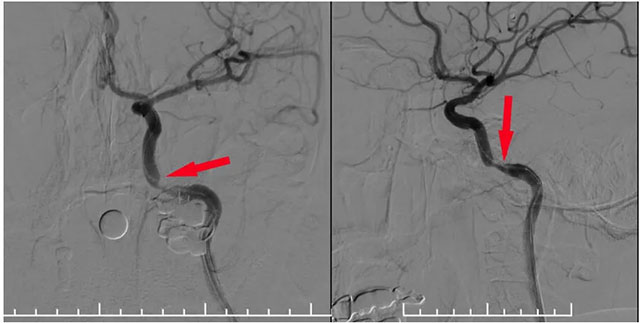

▲ 球囊扩张支架在微导丝导引下到位于狭窄段

▲ 球囊扩张后支架释放狭窄已明显改善

术中,张琪博士在刘春医生、周林华医生及医护团队协助下从左侧股动脉穿刺,置入6F导管鞘。将6F导引导管在泥鳅导丝导引下置入左侧颈内动脉,造影明确岩骨段狭窄呈,测量狭窄段长度及近远端血管支架,选择合适支架,随后在微导丝辅助下越过狭窄段超选至C6段,选用4.0*18球扩支架,沿微导丝到位狭窄段,球囊扩张至6atm,即刻释放支架,即刻造影见狭窄明显改善,支架贴壁良好,血流通畅,狭窄段完全覆盖。